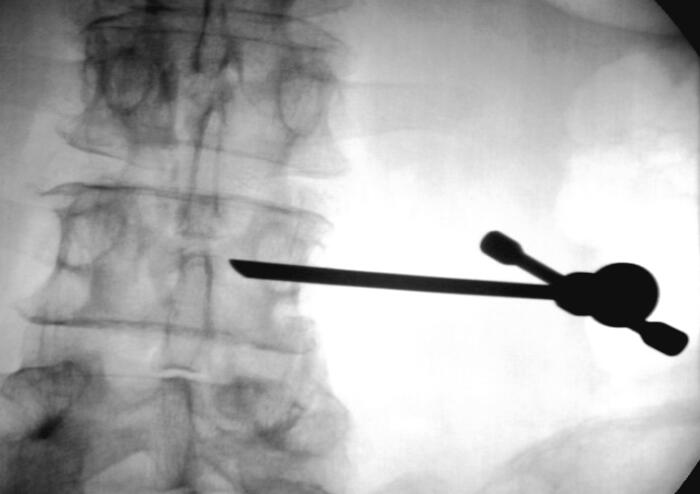

【手術過程演示,神奇的椎體成形術原來如此簡單!】

1、插入穿刺針

4、單側(cè)穿刺入路